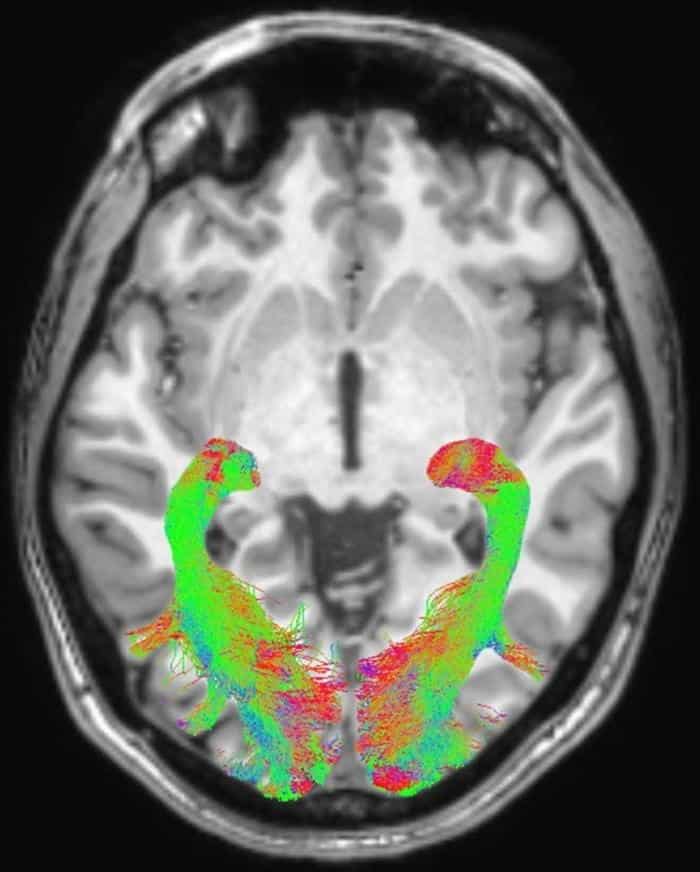

وقد شملت الدراسة 20 مريضا مصابين بمرض باركنسون تم تشخيصهم حديثا ولم يعالجوا بعد (11 رجلا و 9 نساء) و 20 شخصا آخرين غير مصابين متطابقين مع المجموعة الأولى المصابة في السن والجنس، وشارك فيها فريق متعدد التخصصات من الباحثين في طب العيون والأعصاب في جامعة ميسينا – إيطاليا. وتم إجراء تصوير بالرنين المغناطيسي لكلا المجموعتين. وقد استخدم الباحثون تقنية خاصة من التصوير بالرنين المغناطيسي لتحديد كمية المادة البيضاء في المسارات البصرية، كما خضع المشاركون في التجربة كذلك لفحص العيون التقليدي .

وقد وجد الباحثون تغييرات كبيرة في المسارات البصري لمرضى باركنسون، بما في ذلك المادة البيضاء في المتصالبة العصبية- optic chiasm.